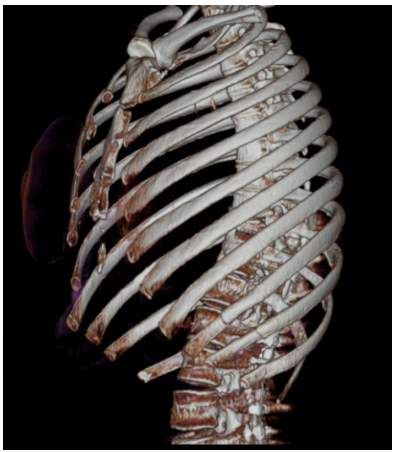

Mulher, 46 anos de idade, apresentou trauma torácico em acidente com queda da motocicleta. Foi realizada a tomografia computadorizada de tórax, conforme imagem a seguir:

Enunciado 4806624-1

Em relação ao caso descrito, assinale a alternativa que apresenta os sinais/sintomas clínicos típicos dos achados da tomografia apresentada.